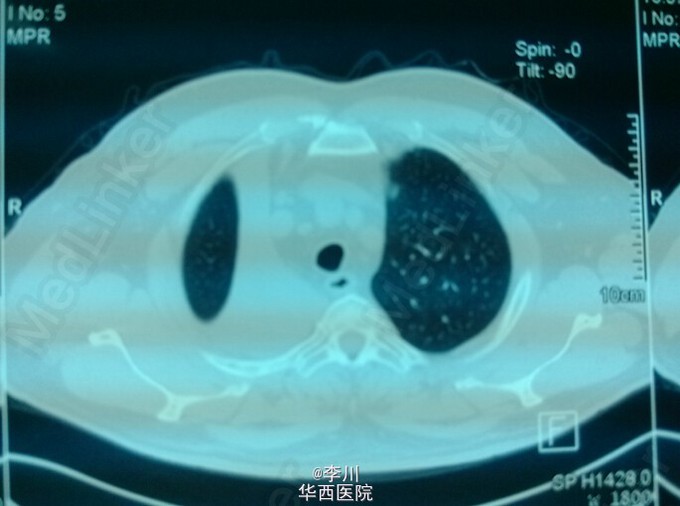

大医院技术更好?---右上肺鳞癌伴肺不张一例

患者为50岁男性,因咳嗽咳痰、痰中带血3+月入院。3+月前患者因上述症状于当地医院就诊,行相关检查后诊断为右肺上叶鳞癌。却被告知不能手术,只能放化疗。患者不甘心,遂于我院就诊,经我院知名专家详细读片评估后,认为有手术指证,首选手术治疗。查体心腹无特殊异常。右上肺呼吸音弱,未闻及干湿罗音,左肺呼吸音无明显异常。